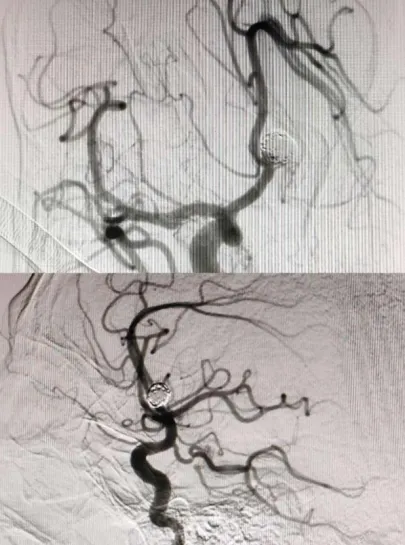

近日,滄州市中心醫(yī)院神經(jīng)血管介入二科為一名突發(fā)蛛網(wǎng)膜下腔出血的患者實(shí)施手術(shù),成功“拆彈”,使患者轉(zhuǎn)危為安。 據(jù)了解,患者陳先生(化名),55歲,在某天夜間突然感到劇烈頭痛,并伴有惡心和嘔吐癥狀,這些癥狀持續(xù)了整整一天。入院1小時(shí)前,他的不適感愈發(fā)明顯,逐漸陷入昏迷狀態(tài),對疼痛刺激已無反應(yīng)。家屬見狀,立即將陳先生送往當(dāng)?shù)蒯t(yī)院就診。醫(yī)生迅速對陳先生進(jìn)行了初步檢查,結(jié)合患者的癥狀和病史懷疑陳先生可能因動(dòng)脈瘤破裂導(dǎo)致蛛網(wǎng)膜下腔出血,情況十分危急。于是,當(dāng)?shù)蒯t(yī)生立即聯(lián)系滄州市中心醫(yī)院神經(jīng)血管介入二科團(tuán)隊(duì),家屬在了解清楚情況后,果斷決定帶患者轉(zhuǎn)往滄州市中心醫(yī)院。 (圖一) 患者到達(dá)滄州市中心醫(yī)院后,神經(jīng)血管介入二科團(tuán)隊(duì)立即展開了緊張的救治工作,迅速為陳先生安排了腦血管造影檢查。造影結(jié)果清晰地顯示:陳先生右側(cè)前交通動(dòng)脈瘤成囊狀,相對寬頸,大小約為7.0*6.9*4.2mm,瘤頂指向上方,形態(tài)不規(guī)則。同時(shí),左側(cè)大腦前動(dòng)脈顯影良好,其余血管未見明顯異常(圖一)。 (圖二) 面對如此緊急和復(fù)雜的病情,神經(jīng)血管介入二科團(tuán)隊(duì)?wèi){借豐富的經(jīng)驗(yàn)和精湛的技術(shù),迅速制定了詳細(xì)的手術(shù)方案——全麻下行顱內(nèi)動(dòng)脈瘤介入栓塞術(shù)。微導(dǎo)管選擇好栓塞部位后,依次送入不同規(guī)格的彈簧圈填充動(dòng)脈瘤。最終造影提示動(dòng)脈瘤的栓塞情況良好(圖二),瘤體周圍的血管沒有狹窄,雙側(cè)大腦前動(dòng)脈的遠(yuǎn)端分支顯影良好。整個(gè)造影過程中,患者的生命體征平穩(wěn)。在團(tuán)隊(duì)的共同努力下,手術(shù)順利進(jìn)行,醫(yī)生成功將陳先生體內(nèi)的“炸彈”——?jiǎng)用}瘤進(jìn)行了妥善處理。患者回到病房后,予心電監(jiān)護(hù)和吸氧,給予鎮(zhèn)靜、預(yù)防抽搐、緩解血管痙攣、補(bǔ)充血容量和抑酸等治療。患者恢復(fù)期間病情逐漸好轉(zhuǎn),順利出院。 什么是顱內(nèi)動(dòng)脈瘤? 顱內(nèi)動(dòng)脈壁局限性、病理性膨起,普遍存在于全球成年人群中。顱內(nèi)動(dòng)脈瘤破裂是導(dǎo)致自發(fā)性蛛網(wǎng)膜下腔出血的首位病因,且多發(fā)生在55~65歲的人群中。盡管不同地區(qū)的死亡率有所下降,但大多數(shù)患者仍遺留有明顯的神經(jīng)功能障礙,這給家庭和社會(huì)造成了沉重的負(fù)擔(dān),嚴(yán)重影響了患者的生活質(zhì)量。因此,顱內(nèi)動(dòng)脈瘤是當(dāng)前嚴(yán)重影響到世界人民生命安全的疾病。隨著醫(yī)學(xué)器械技術(shù)的發(fā)展,動(dòng)脈瘤栓塞介入術(shù)、血流導(dǎo)向裝置植入術(shù)、動(dòng)脈瘤夾閉術(shù)等技術(shù)日趨成熟。 姜紅升主任攜領(lǐng)神經(jīng)血管介入二科團(tuán)隊(duì)提醒您:顱內(nèi)動(dòng)脈瘤是腦中的“定時(shí)炸彈”,動(dòng)脈瘤破裂會(huì)導(dǎo)致蛛網(wǎng)膜下腔出血,致殘率高、死亡率高。其主要癥狀為劇烈頭痛,如突發(fā)難以忍受的頭痛癥狀,不容小覷,應(yīng)及時(shí)到醫(yī)院進(jìn)行診治。未出現(xiàn)動(dòng)脈瘤破裂的患者,應(yīng)及時(shí)控制高血壓、糖尿病、高血脂癥、抽煙、酗酒等高風(fēng)險(xiǎn)因素,并及早根據(jù)個(gè)人動(dòng)脈瘤特征選擇合適的治療方式。 神經(jīng)血管介入二科 國家臨床重點(diǎn)??苿?chuàng)建單位,河北省臨床重點(diǎn)建設(shè)??疲瑴嬷菔信R床重點(diǎn)??疲壳皳碛嗅t(yī)護(hù)人員20人、醫(yī)生6人,護(hù)士14人,其中醫(yī)學(xué)博士1人,碩士研究生導(dǎo)師1人,副主任醫(yī)師2人,主治醫(yī)師1人,住院醫(yī)師3人;主管護(hù)師3人,主持科研項(xiàng)目3項(xiàng),榮獲河北省衛(wèi)健委二等獎(jiǎng)1項(xiàng);近三年內(nèi)發(fā)表SCI論文數(shù)篇,其中一篇發(fā)表于中科院分區(qū)1區(qū)雜志。主要診療范圍:腦血管病的外科手術(shù)與介入治療。我科與北京天壇醫(yī)院、宣武醫(yī)院、天津醫(yī)科大學(xué)總醫(yī)院、天津市環(huán)湖醫(yī)院、河北省醫(yī)科大學(xué)第二醫(yī)院、山東大學(xué)齊魯醫(yī)院等長期保持密切的的友好合作關(guān)系,在顱內(nèi)動(dòng)脈瘤、頸動(dòng)脈狹窄等疾病診療方面,神經(jīng)血管介入二科基于疾病特點(diǎn)以及患者具體情況不同,個(gè)體化的為患者制訂適合的手術(shù)方案;我們科室的發(fā)展理念:以患者的醫(yī)療安全為重中之重、嚴(yán)格把控醫(yī)療質(zhì)量、業(yè)務(wù)水平精益求精、通過熱情誠懇的服務(wù)理念,不忘初心、以德立科,在患者朋友們和醫(yī)院內(nèi)外樹立良好的口碑。 科室診療范圍: 1.蛛網(wǎng)膜下腔出血、顱內(nèi)動(dòng)脈瘤開顱夾閉術(shù)、顱內(nèi)動(dòng)脈瘤介入栓塞術(shù)、血流導(dǎo)向裝置植入術(shù)、瘤內(nèi)擾流裝置植入術(shù)等; 2. 腦血管畸形、硬腦膜動(dòng)靜脈瘺的外科手術(shù)切除與介入栓塞術(shù); 3. 顱內(nèi)外血管狹窄、煙霧病等導(dǎo)致的腦梗死、短暫性腦缺血發(fā)作等,頸動(dòng)脈、椎動(dòng)脈、鎖骨下動(dòng)脈支架及顱內(nèi)動(dòng)脈支架植入術(shù)、頸動(dòng)脈內(nèi)膜剝脫術(shù)、顱內(nèi)外血管搭橋術(shù); 4. 急性腦梗塞動(dòng)脈溶栓、取栓術(shù); 5. 靜脈竇血栓形成溶栓、取栓術(shù),良性顱內(nèi)壓增高綜合征,靜脈竇支架置入術(shù)、巖下竇采血輔助診斷垂體瘤等; 6. 慢性頸動(dòng)脈閉塞再通術(shù)、腦血管畸形介入栓塞+外科手術(shù)切除等、顱內(nèi)高血運(yùn)腫瘤術(shù)前供血?jiǎng)用}栓塞等復(fù)合手術(shù); 7. 脊髓血管造影,硬脊膜動(dòng)靜脈瘺栓塞術(shù); 8. 神經(jīng)危重癥的救治。 門診地址:滄州市中心醫(yī)院腦科院區(qū)北2樓1診室 病區(qū)地址:滄州市中心醫(yī)院腦科院區(qū)北6樓 科室電話:0317-2179505 姜紅升 神經(jīng)血管介入二科副主任(主持工作),黨支部書記,醫(yī)學(xué)博士,碩士研究生導(dǎo)師,副主任醫(yī)師,畢業(yè)于天津醫(yī)科大學(xué)神經(jīng)外科專業(yè),先后于北京天壇醫(yī)院、復(fù)旦大學(xué)華山醫(yī)院、天津醫(yī)科大學(xué)總醫(yī)院、山東大學(xué)齊魯醫(yī)院等學(xué)習(xí)進(jìn)修,主要擅長腦血管疾病的外科手術(shù)及介入治療。主持科研項(xiàng)目多項(xiàng),榮獲河北省衛(wèi)健委二等獎(jiǎng)一項(xiàng)。 專業(yè)擅長:腦動(dòng)脈瘤、血管狹窄、動(dòng)靜脈畸形、煙霧病等腦血管病的手術(shù)及介入治療。